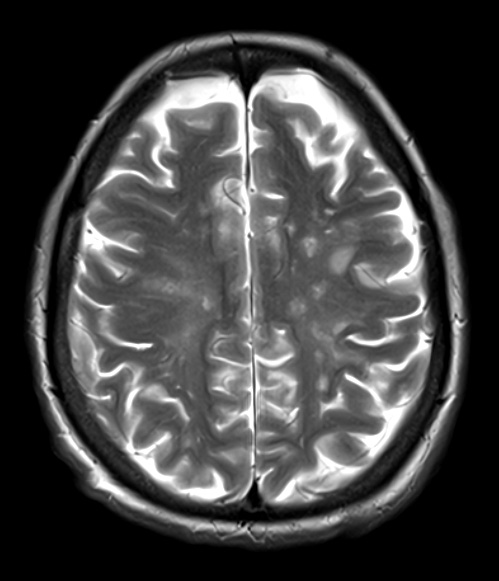

A T2 weighted MRI without contrast shows hyperintense lesions with a predilection for the white matter.